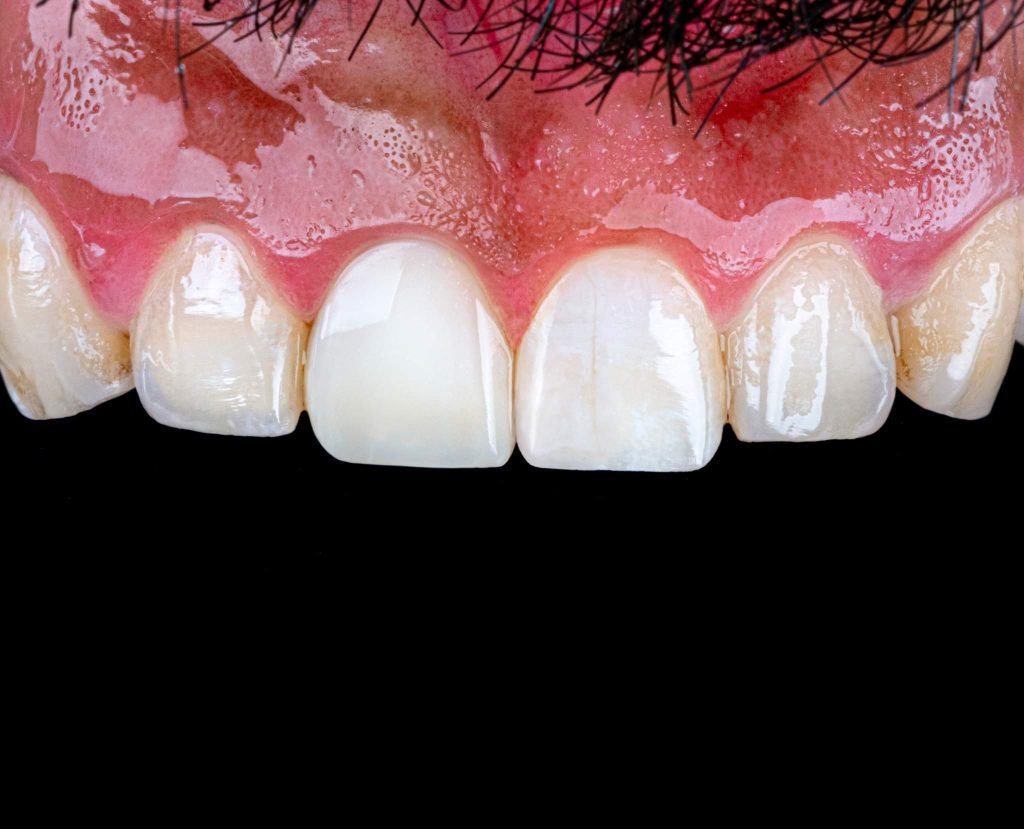

This is a case of discolored right central incisor for a 21 years-old-male patient. He had a history of previous trauma 2 years ago to his tooth and fracture, that was managed with a composite restoration. After clinical examination and x-ray imaging, the tooth was non-vital with periapical lesion.

After discussing the treatment options with the patient, he chose the direct composite veneer. The treatment included endodontic treatment, internal bleaching, direct composite veneer for the right central, and aesthetic reshaping for the laterals and left incisor also by composite restoration. The case completed in 2 sessions.